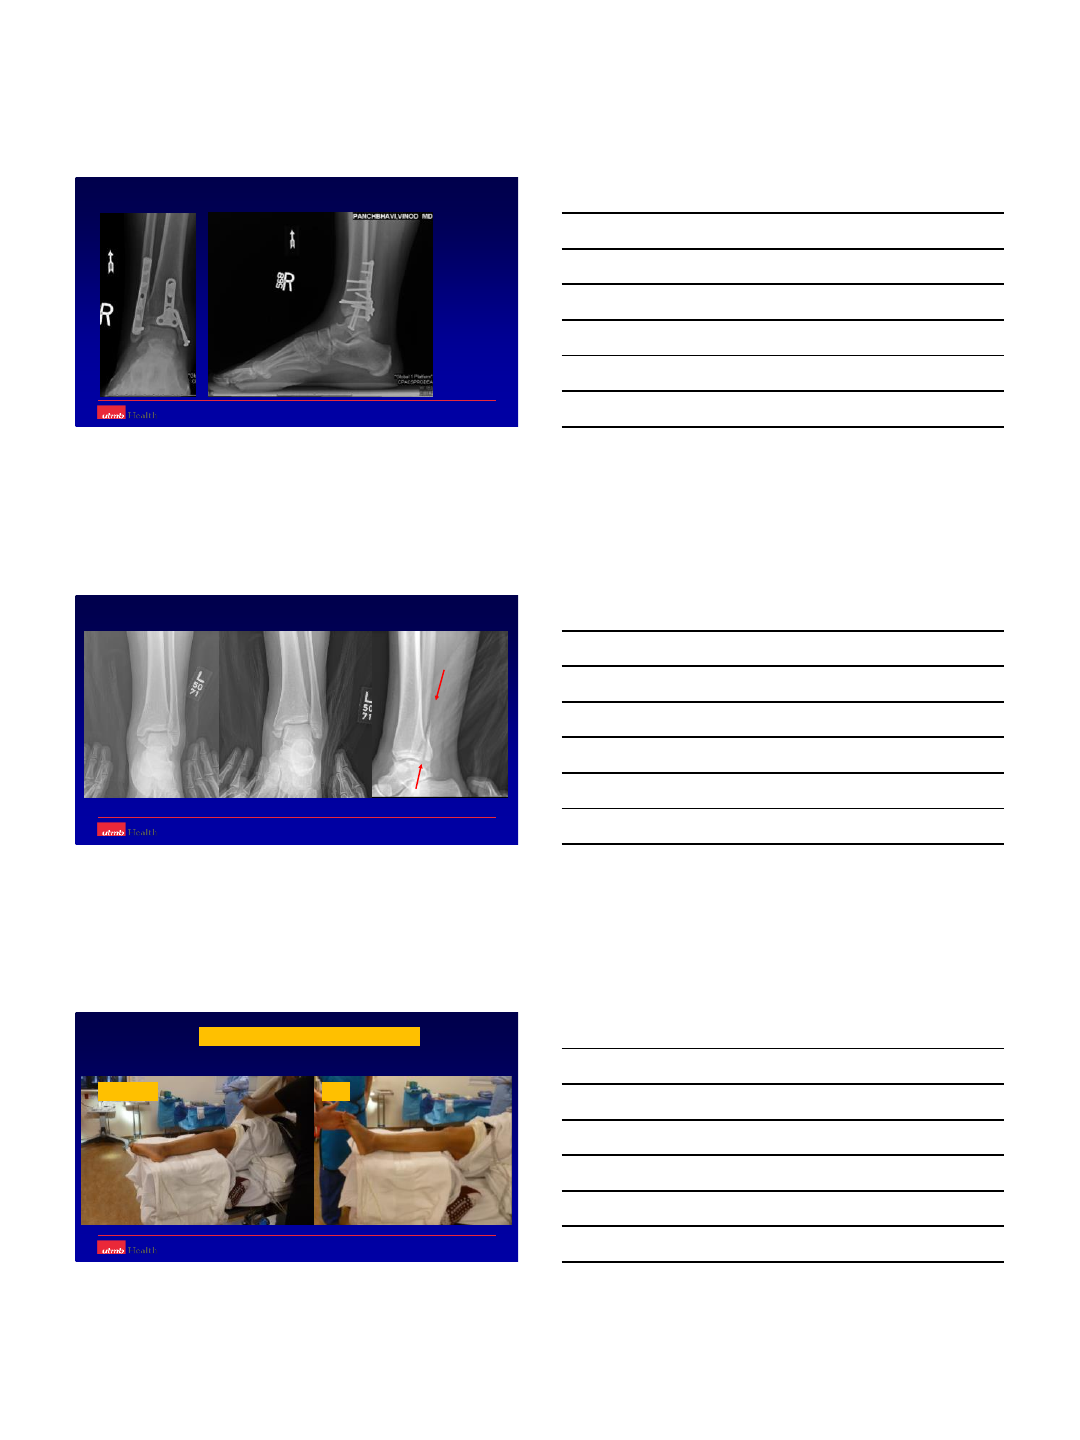

Case 1

-58 year old WM

comes with 2 weeks

history of trivial

trauma.

-Presentation in the

clinic walking without

any support.

-Pain level 2/10

-Is it normal???

-Am I missing something here??

Case 3

-47 year old female

with ORIF ankle

fracture [1 year ago],

still complaining about

7/10 pain with

ambulation.

-Fracture seems to be

healed but what next??